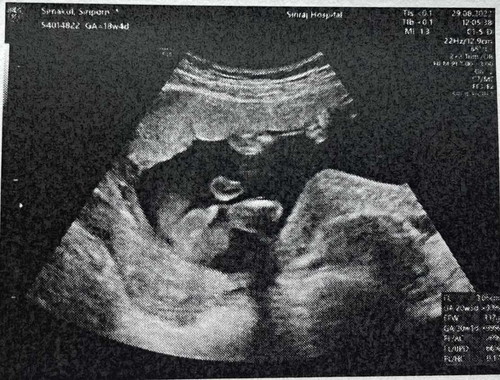

เมื่อวานไปซาวมา ป้าหมอบอกได้ ผช 100% แม่นี่มึนตึ๊บเลยเพราะคิดชื่อลูกไม่ออกอยากให้คล้องกับพี่สาวที่ชื่ออันดามัน